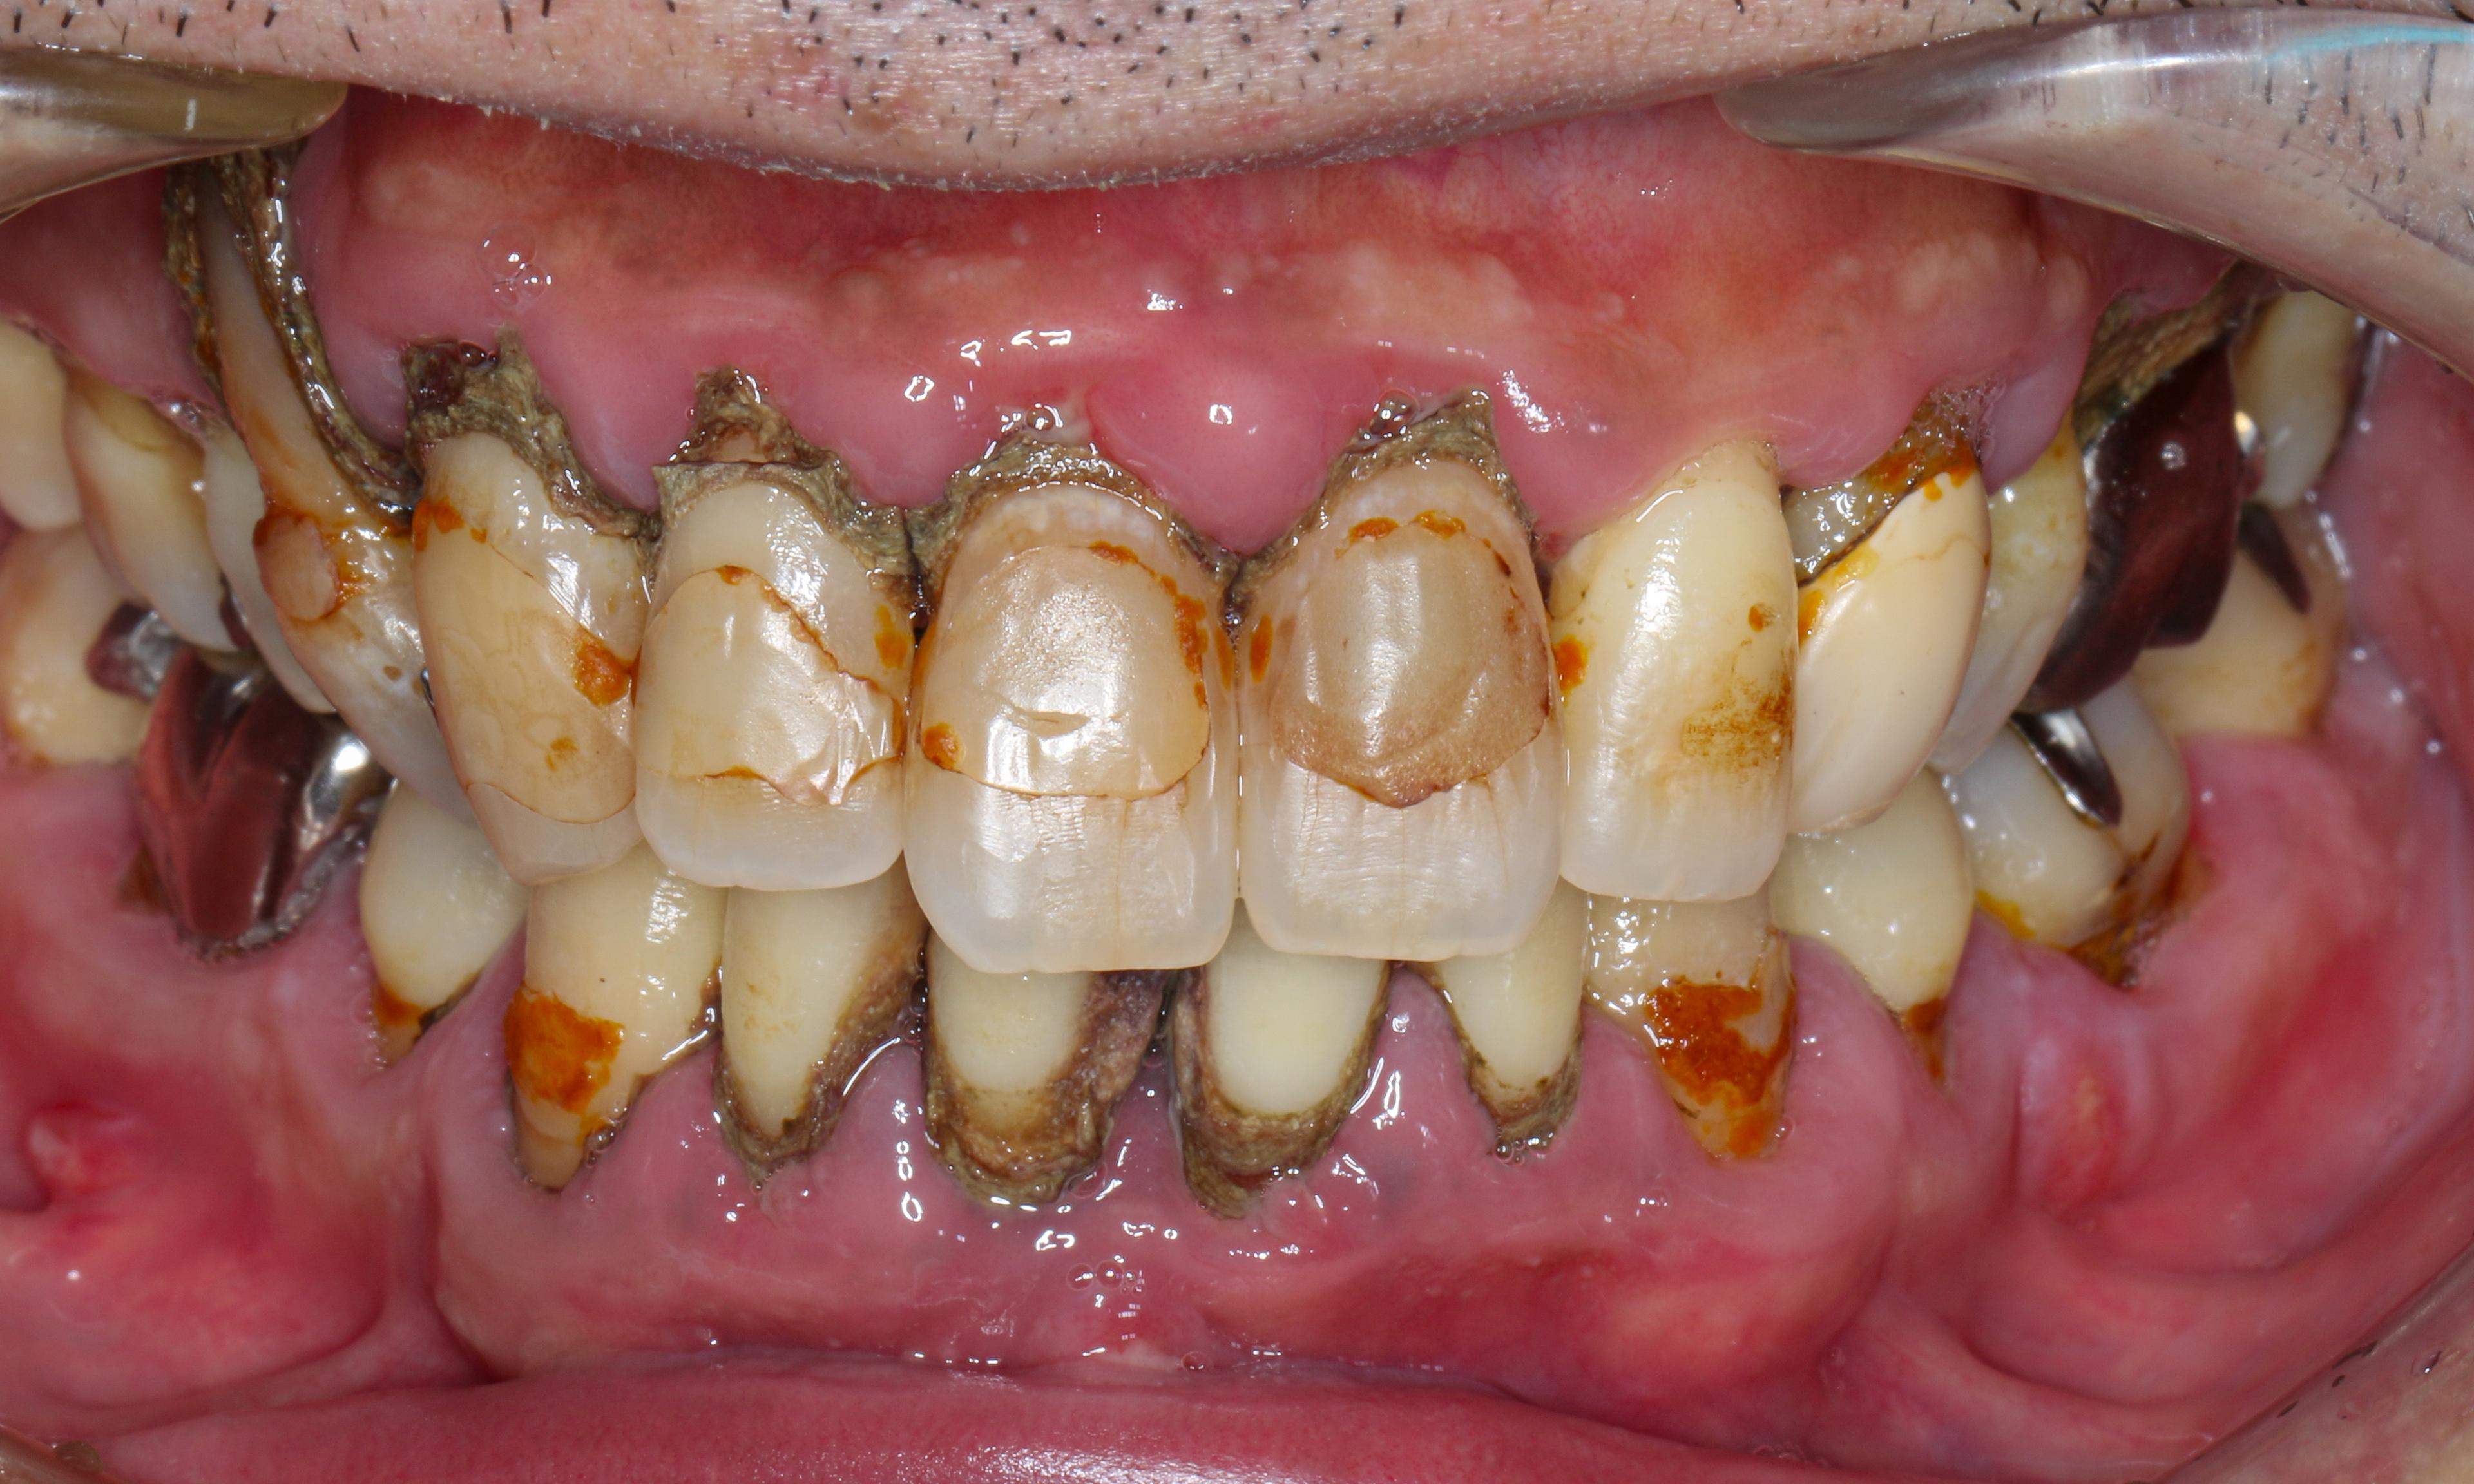

歯周ポケット測定不能。教科書的に100%抜歯の重度慢性歯周炎。原因除去療法とマイクロスコープを使った低侵襲の歯周組織再生療法により、抜歯を回避して回復した症例です。

ポケットの深さ測定不能

指数病の治療をしたいということでご来院された40代の男性です。写真で分かるとおり歯石がびっしりと着いており歯周炎により歯茎の腫れも相当ある状態でした。

- 広汎型慢性歯周炎 ステージ3 グレードC

と診断をいたしました。